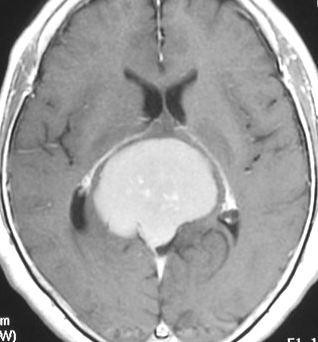

典型的な髄膜腫

この髄膜腫は中程度の大きさのものです。円蓋部髄膜種という最も多い最も手術の簡単なタイプです。麻痺や失語症やてんかんなどの症状はありません。とても美しくて若い女性の髄膜腫でしたが,子供に遺伝はしませんし,癌などと違ってタバコなどこれといった原因がなくて発生するものです。

MRIでの髄膜腫の見え方は撮影の仕方によっていろいろです。左からT1強調画像,T2強調画像,フレア画像といいます。腫瘍の横に小さく白い領域がありますが,これは脳の腫れた部分で脳浮腫といいます。髄膜腫があると周囲に脳浮腫が生じることがあります。

最も見やすいのが,ガドリニウム造影剤を注射して撮影するものです。一般的に髄膜腫は造影剤で白く映し出されます。この腫瘍は左脳側にあります。MRIの軸面という輪切りの写真では左右が逆になりますから注意してください。脳を下から見た図になっています。MRIはいろいろな方向から腫瘍を見ることができますが,右は冠状断という正面から見た図です。よく見ると腫瘍の上と下のはじっこに線状に糸を引いたように造影される部分があります。これをテールサイン(しっぽのサイン)といいます。腫瘍が硬膜に沿って延びている可能性があることを示しています。

手術後のMRIです。腫瘍は全部取れていて後遺症もありません。圧迫されて変形していた脳はきれいに元に戻っていますし脳浮腫も消えました。一般的に若い人の脳ほどきれいに元に戻ります。注意しなければならないのは,少しでも取り残した場合には,何年か後に10%-20%くらいで再発があることです。もちろん完全に取れた時の再発はほとんどありません。